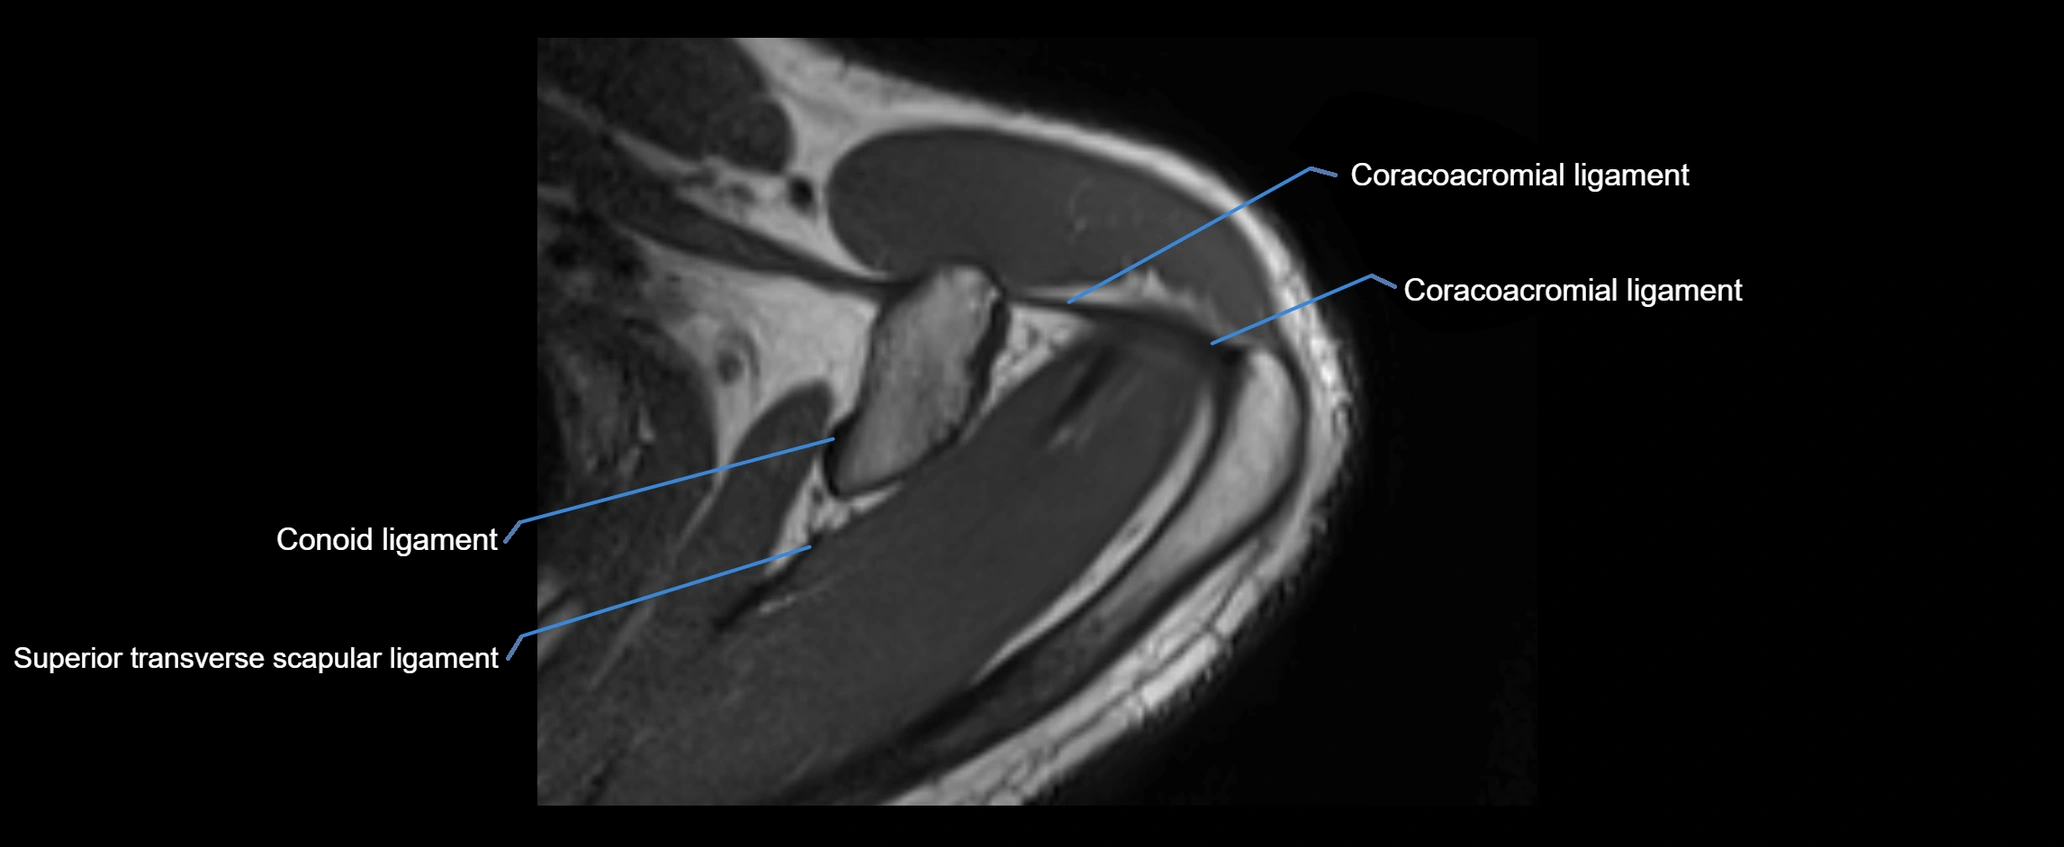

MRI images

image